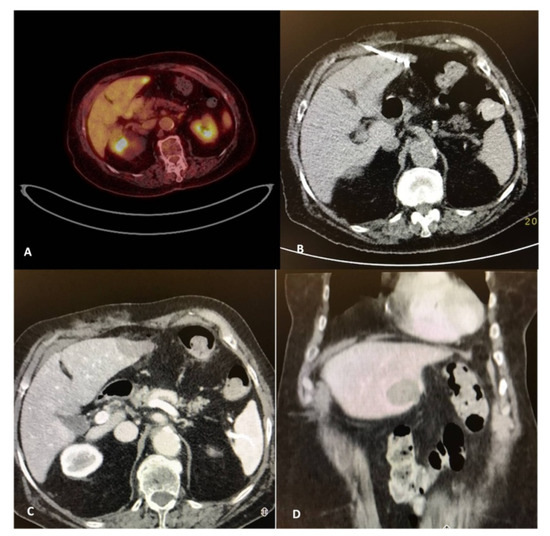

- Cornelis, F.; Sotirchos, V.; Violari, E.; Sofocleous, C.T.; Schoder, H.; Durack, J.C.; Siegelbaum, R.H.; Maybody, M.; Humm, J.; Solomon, S.B. 18F-FDG PET/CT is an immediate imaging biomarker of treatment success after liver metastasis ablation. J. Nucl. Med. 2016, 57, 1052–1057. [Google Scholar] [CrossRef]

- Mauri, G.; Gennaro, N.; De Beni, S.; Ierace, T.; Goldberg, S.N.; Rodari, M.; Solbiati, L.A. Real-time US-(18)FDG-PET/CT image fusion for guidance of thermal ablation of (18)FDG-PET-positive liver metastases: The added value of contrast enhancement. Cardiovasc. Intervent. Radiol. 2019, 42, 60–68. [Google Scholar] [CrossRef]

- Ryan, E.R.; Sofocleous, C.T.; Schöder, H.; Carrasquillo, J.A.; Nehmeh, S.; Larson, S.M.; Thornton, R.; Siegelbaum, R.H.; Erinjeri, J.P.; Solomon, S.B. Split-dose technique for FDG PET/CT-guided percutaneous ablation: A method to facilitate lesion targeting and to provide immediate assessment of treatment effectiveness. Radiology 2013, 268, 288–295. [Google Scholar] [CrossRef]

- Cornelis, F.H.; Petre, E.N.; Vakiani, E.; Klimstra, D.; Durack, J.C.; Gonen, M.; Osborne, J.; Solomon, S.B.; Sofocleous, C.T. Immediate postablation 18F-FDG injection and corresponding SUV are surrogate biomarkers of local tumor progression after thermal ablation of colorectal carcinoma liver metastases. J. Nucl. Med. 2018, 59, 1360–1365. [Google Scholar] [CrossRef]